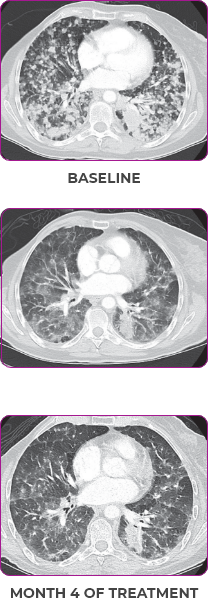

76-YEAR-OLD FEMALE WITH BRAIN METASTASES1

NSCLCa PATIENT WITH BRAIN

METASTASES1-3

- 76-year-old female with NSCLC that metastasized to the brain and liver

MRIa imagery of the brain. Green circles indicate baseline brain metastases.1

SCAN 2: BRAIN

aMRI, magnetic resonance imaging.

MRIa imagery of the brain. Green voxels indicate decreased burden of metastatic disease; further quantified by accompanying measurement in green.1

Response in primary and metastatic lesions1

SCAN 3: BRAIN